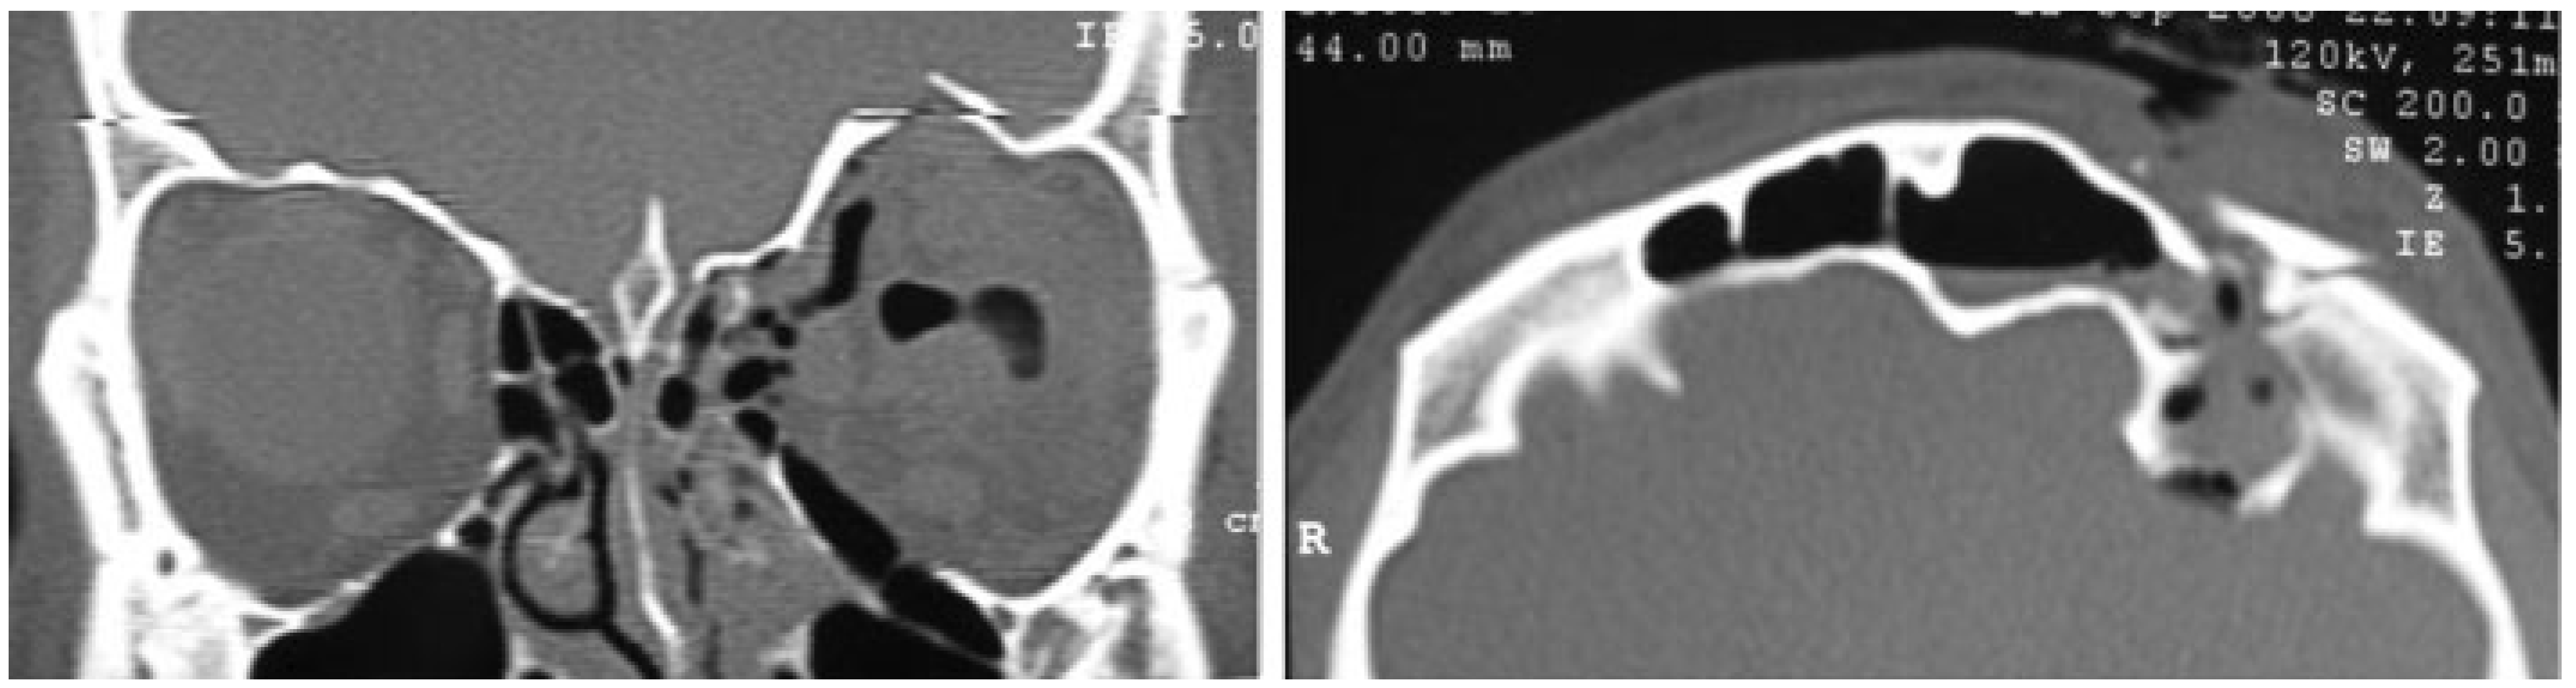

A 30-year-old man with male pattern baldness was referred to our department for a craniomaxillofacial trauma caused by a motorcycle accident. He presented left periorbital ecchymosis and edema, subconjunctival hemorrhage, eyelid ptosis, eyelid lacerations, enophthalmos, and pain during eye movements, along with diplopia (Figure 7). A CT scan showed displaced fracture of left frontal sinus anterior wall, nondisplaced fractures of frontal sinus posterior wall, and blowout fractures of the inferior, medial, and superior left orbital walls with dural laceration, needing combined neurosurgical and maxillofacial repairs (Figure 8). With a left unilateral zigzag pretrichial incision, we were able to widely expose the frontal sinus anterior wall fracture. Through a craniotomy, performed by a neurosurgeon, the damaged left orbital roof was reduced. The frontal sinus was then obliterated with abdominal fat and stabilized with microplates and screws (Figure 9). Finally, inferior and medial orbital walls were reconstructed with polyethylene implants (Medpor, Strykez Corporation, Newnan, Georgia) using a Lynch incision and a transconjunctival incision. A postoperative CT scan confirmed a correct surgical reduction (Figure 10). The pretrichial incision healed without aesthetic complications (Figure 11) and after 30 months of follow-up, the scar is insignificant (Figure 12).

Figure 10. Case 8. Postoperative coronal and 3-D computed tomography images.